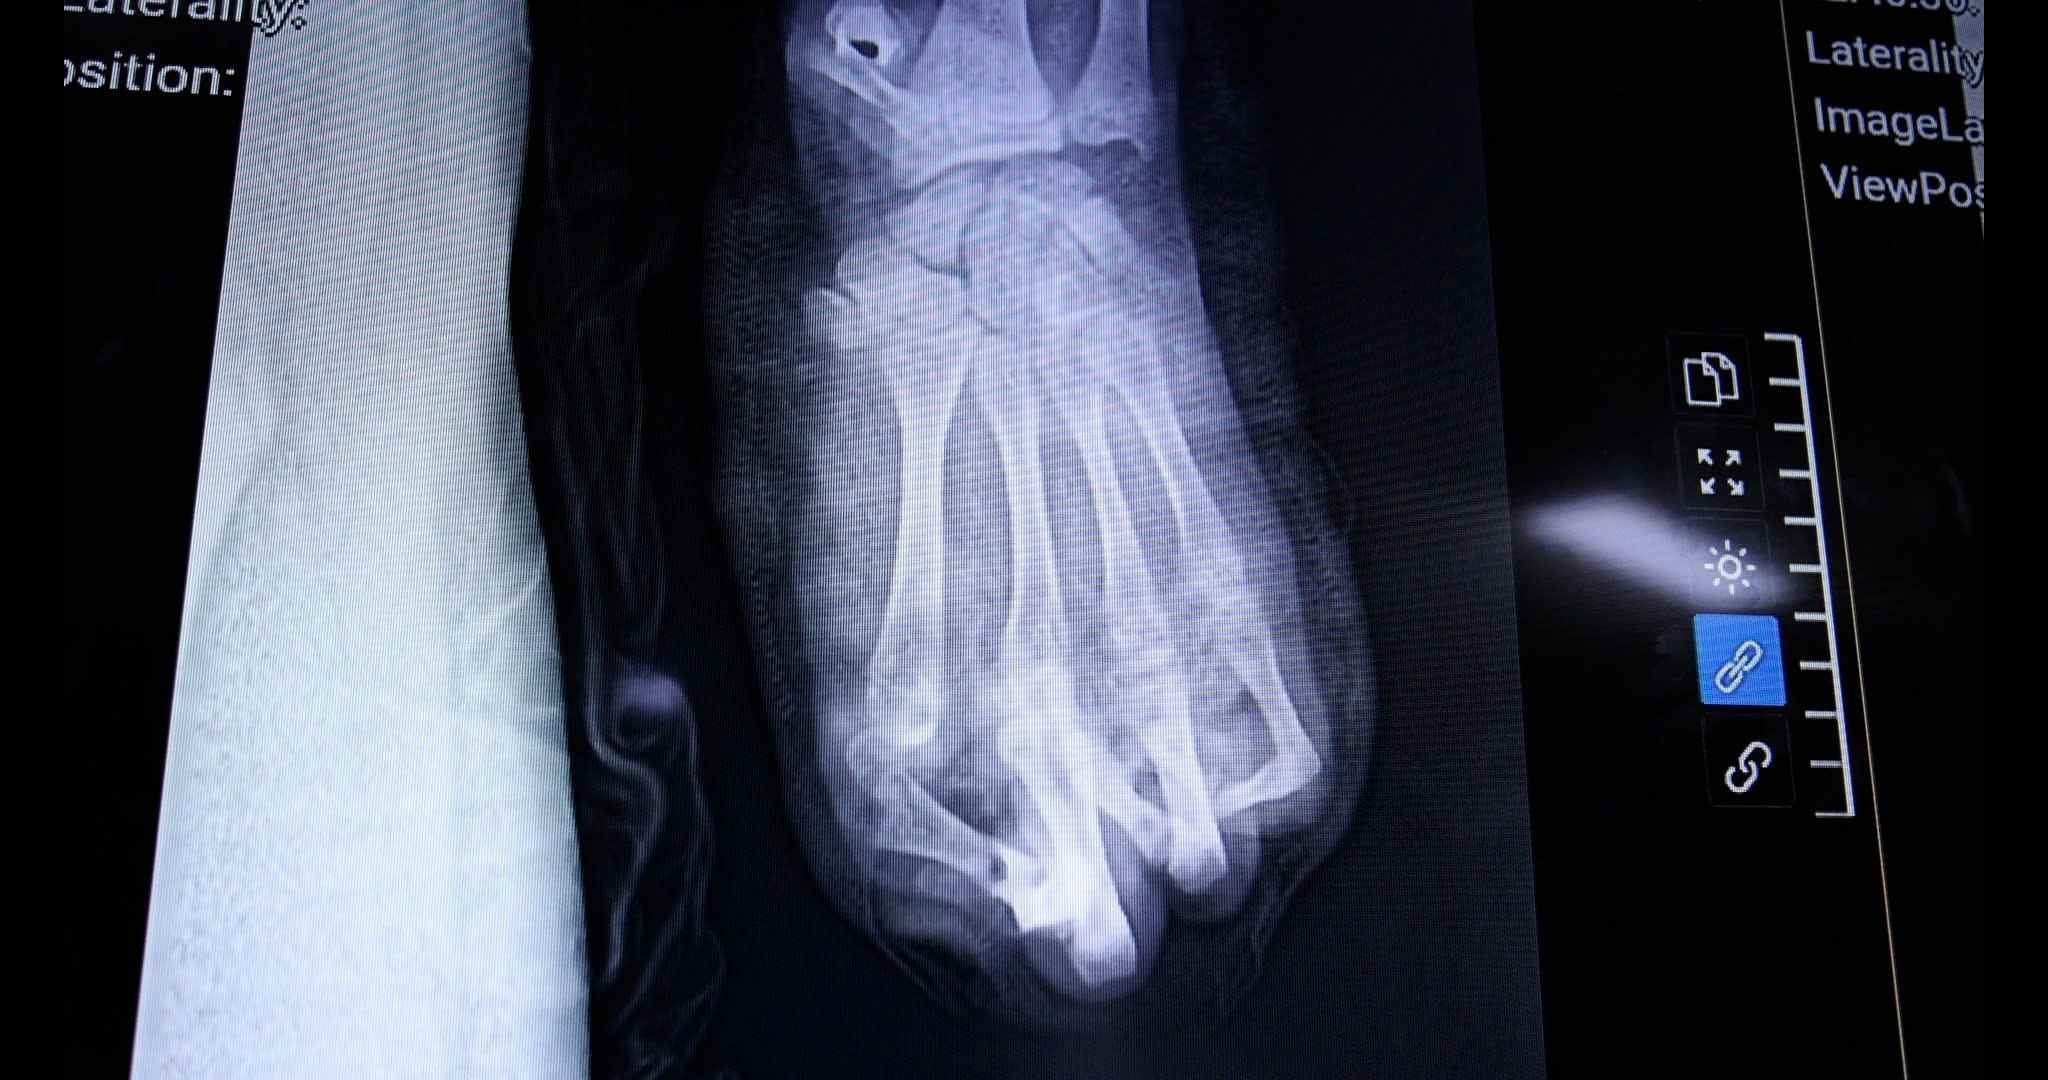

On the same night, the surgical team urgently carried out emergency treatment, cutting off the crushed tissue, removing the foreign objects that were firecracker fragments. However, after many hours of effort, the doctors could only keep 2 out of 5 fingers. The entire liver and wrist area were severely destroyed, causing a very high risk of hand loss.

According to doctors, the treatment process for the patient will be prolonged with many subsequent surgeries. In the immediate future, the patient needs to be covered with skin patches to the necrotic areas. In the next few months, if conditions permit, doctors are expected to perform surgery to move the toe up to replace the lost thumb.

However, the long-term prognosis is still very hesitant. Patients are likely to have to accept permanent loss of at least 2 fingers and can only recover a very limited part of the function of the left hand.